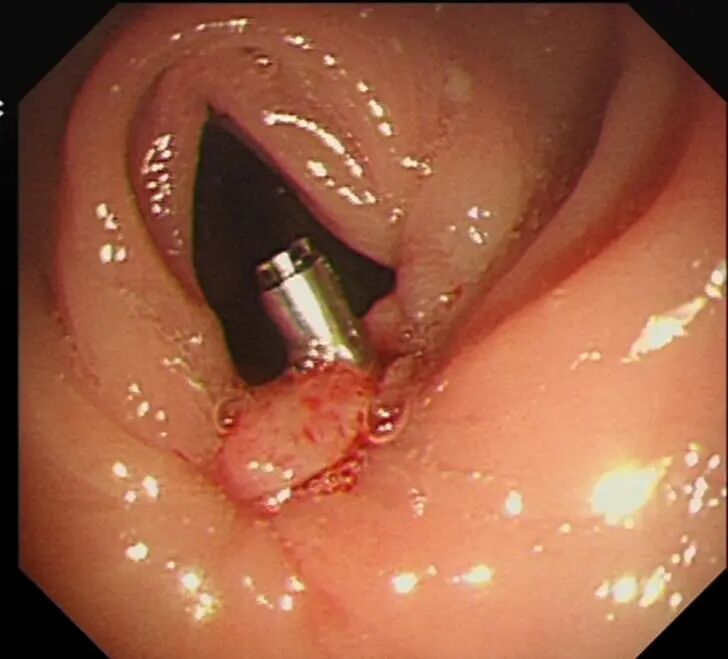

瘤体ESD术

切除中

经过数小时的努力,手术过程顺利,肿瘤被完整切除,切下来的组织送检后发现病变部分已进展至癌,为早期直肠癌。术后温大爷恢复良好,已能正常进食,并顺利出院。